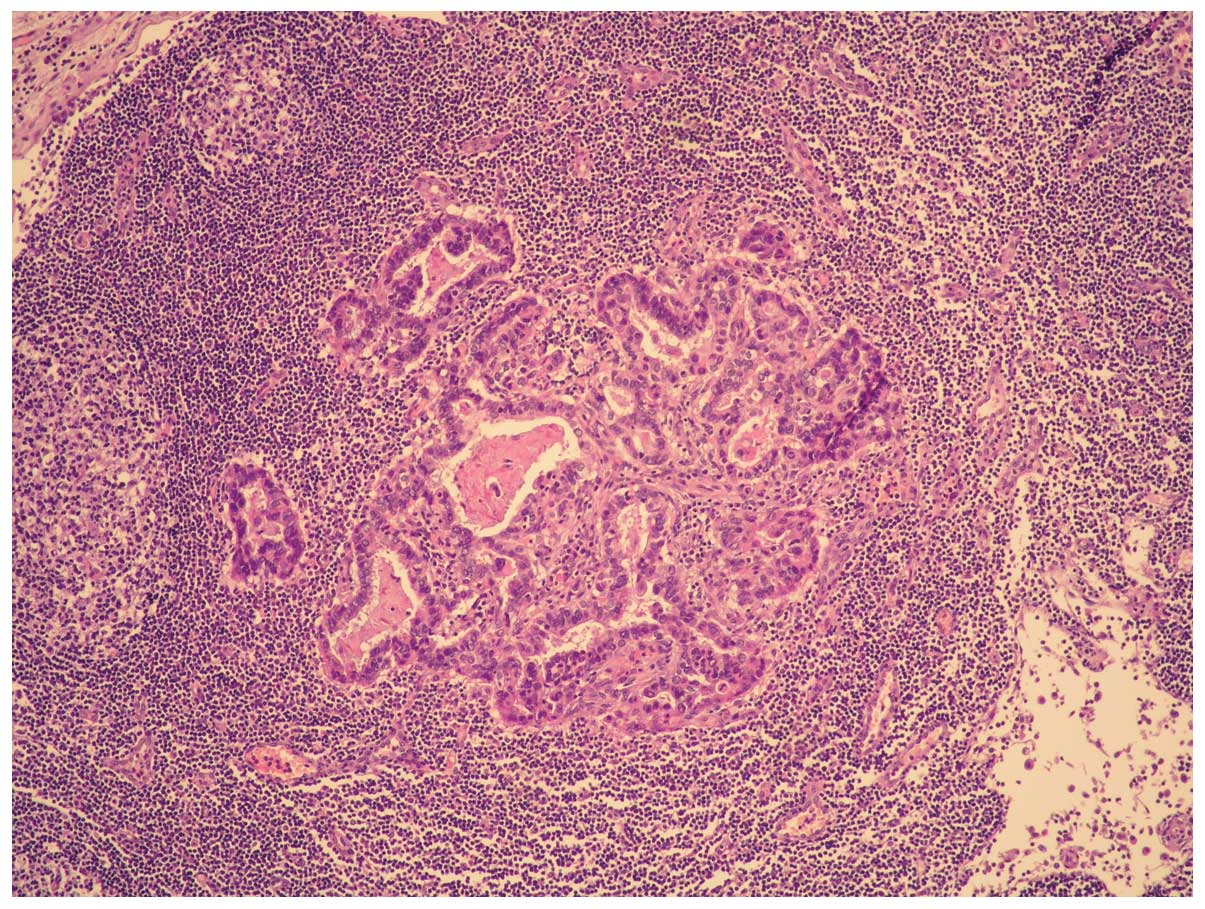

Microscopically, the tumor was composed of moderately

differentiated adenocarcinoma and poorly differentiated sarcoma

with a high mitotic index and necrotic areas (Figs. 1 and 2).